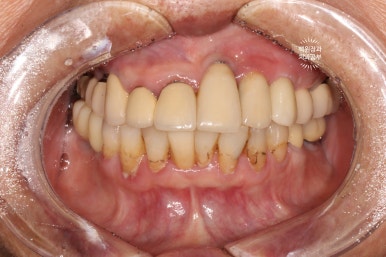

Before & After

정면 사진이 가장 드라마틱한데요,

일단 철저한 스케일링과 잇몸치료 그리고 함께 했던 착색제거술로 전반적으로 깨끗해진 구강내 환경을 보실 수 있어요!!! 다만, 아래 앞니에 있던 치아 목부위 레진들의 착색은 완전히 제거하지 못했답니다... 이는 다시 떼워야 해결이 되어요!

그리고 아래 앞니 한 곳은 지르코니아 크라운으로 씌워드렸고, 가지런히 깨끗깨끗~